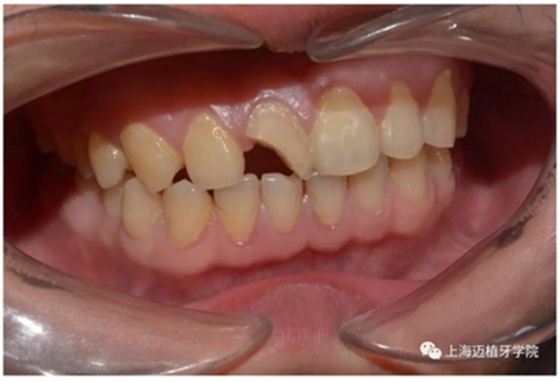

術(shù)前照片

主訴:前門外傷牙根折要求修復(fù)?現(xiàn)病史:前門牙外傷,劈裂至根部,無法固定及其他修復(fù),要求種植?檢查:11牙冠2/3缺損,唇腭向劈裂,唇部紅腫。 CT示根折, 骨寬度9.47mm,距鼻底12.34mm,Ⅲ類骨。 口腔衛(wèi)生一般